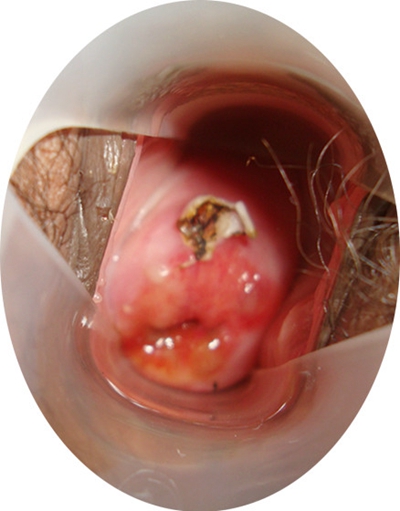

子宮頸癌前病變圖片

宮頸癌的早期症狀

宮頸癌的早期症狀

宮頸癌的早期症狀

宮頸癌的早期症狀

宮頸癌的早期症狀

宮頸癌的早期症狀

宮頸癌的早期症狀

宮頸癌的早期症狀

宮頸癌的早期症狀

宮頸癌的早期症狀